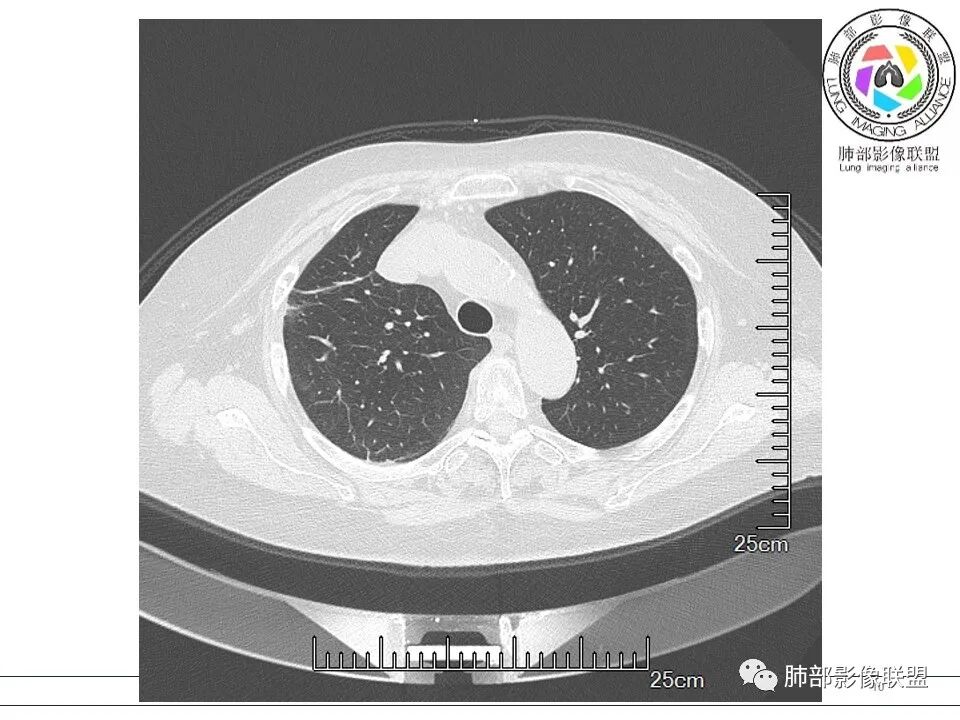

宇宙: 右肺上叶胸膜下结节,多结节融合,长轴平行胸膜,边缘模糊,周围长索条,胸膜牵拉,近端支气管充气扩张,考虑隐球菌,鉴别OP

黄棘: 右肺上叶近胸膜下病灶,多个融合,边缘清,与胸膜平行分布,支气管进入后堵塞,周围见多发长索条影,考虑隐球菌

果哣.: 右肺上叶靠近胸膜结节影,平直为主,边缘清晰,支气管进入后截断,有扩张,考虑炎性隐球菌可能

衡妈: 老年女性,右肺上叶沿胸膜下不规则实性病灶,长轴平行于胸膜,有结节融合感,边缘部分彭隆部分平直,周围可见数条纤维灶影,病灶内可见充气支气管征未达远端,首诊考虑慢性炎性肉芽肿,隐球菌?机化性肺炎?建议增强扫描及ct下穿刺活检。

放射线 (王秀仙): 右肺上叶胸膜下结节样影,边缘平直收缩,胸膜牵拉,支气管进入病灶并扩张,部分支气管进入后阻塞,长轴平行于胸膜,周围可见片状及条索状影,隐球?机化性肺炎?

良孑: 右肺胸膜下多发结节,长轴与胸膜平行,部分病灶有多结节融合,可见近端支气管充气征,有晕征及晕中软毛刺,长期口服激素病史,抗炎效果欠佳。病灶形态单一,无播散性树芽,结节内无支气管穿行,单侧发病,收缩力差,可排除TB,OP及淋巴瘤,综和考虑支持隐球菌

5、分布:隐球菌肺炎是肺泡性炎症,病灶分布多位于胸膜下,可紧贴胸膜,也可与胸膜邻近,病灶长轴与胸膜平行。(划重点,分布特点非常重要,因为隐球菌如果没有荚膜,会被巨噬细胞吞噬,在人体内是无法生存。隐球菌孢子吸入后,要有高浓度的CO2的条件下,才能形成荚膜,所以肺泡内、胸膜下多见)